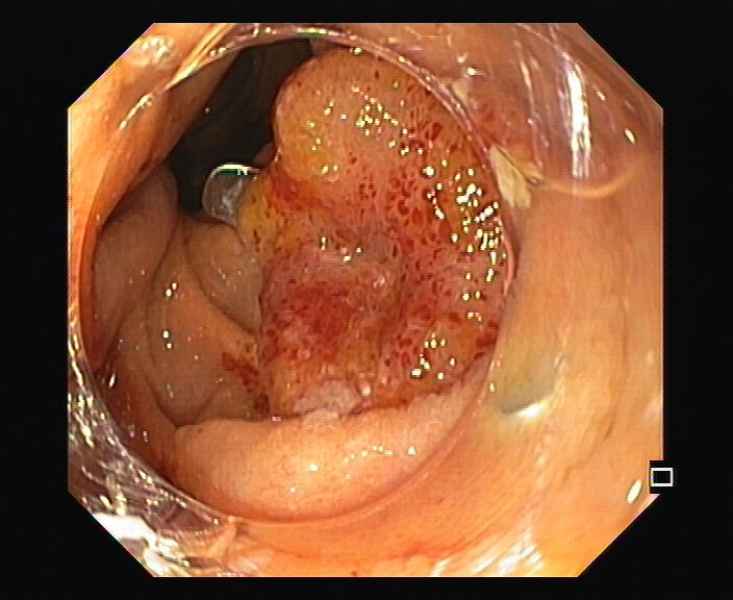

From IPMN to IPMN-derived invasive adenocarcinoma